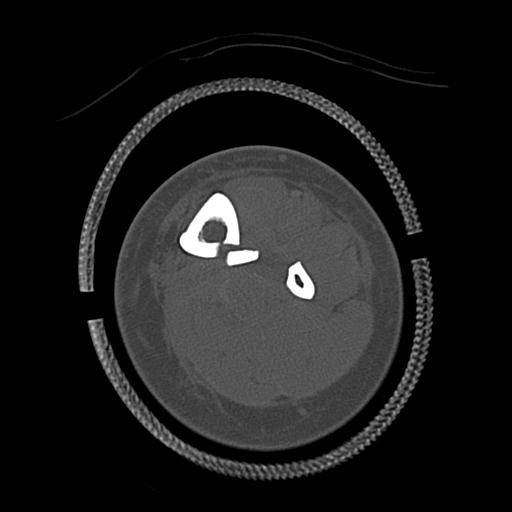

56476 8/28 4R 1/21 2R 左足関節 デジカメ写真 72歳女性 右足関節AS

102755 1/4 2R 1/15 2R 右足関節 68歳女性 右三果脱臼骨折